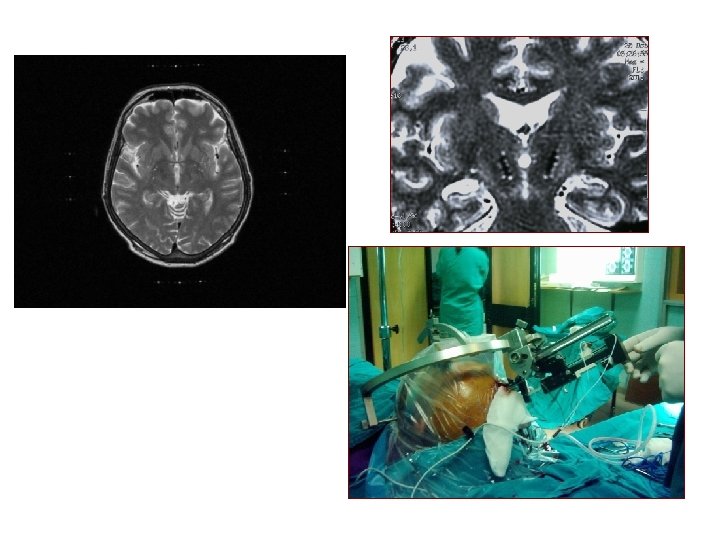

Parkinson Hastalığı’nın Cerrahi Tedavisi Kapsüla internagenus (dizartri) ÖN KAUDAT ÇEKİRDEK Dorsomedial çekirdek (demans) İÇ Ventralis lateralis Ventralis intermedius Ventral posterolateral TALAMUS (hemihipoestezi) Ventral posteromedian (dizartri) ARKA PUTAMEN Globus pallidumpars DIŞ interna Kapsula internaarka bacak (hemiparezi, hemidistoni, hemihipoestezi)

Parkinson Hastalığı’nın Cerrahi Tedavisi ÜST TALAMUS Kapsüla interna PUTAMEN İÇ DIŞ SUBTALAMİK ÇEKİRDEK PALLİDUM Substansiya nigra (parkinsonizmde artış, okülojirik kriz) ALT Optik traktus (görme alanı defektleri)